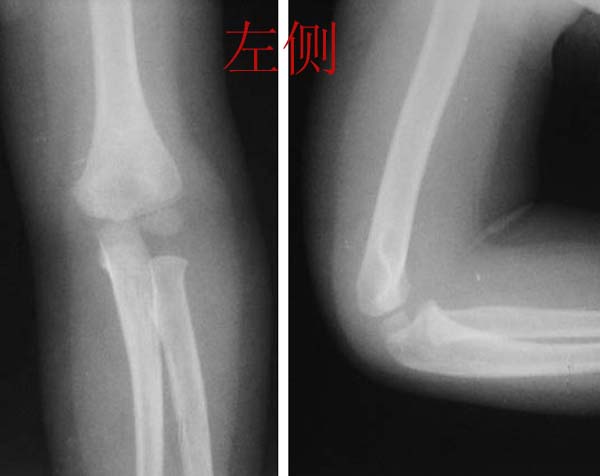

感谢大家的热烈讨论,应大家的要求,今天发右侧肘关节片,请大家继续讨论,讨论时对小儿肘关节二次骨化中心的多少、出现和闭合时间以及骺离骨折的判断和分型进行分析。

双侧对称,说明左侧肘关节骨质正常.